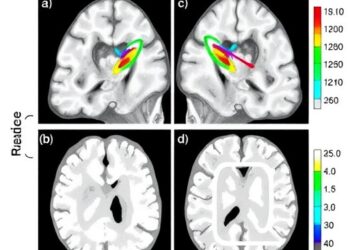

White Matter Changes in 15q11.2 CNV Carriers